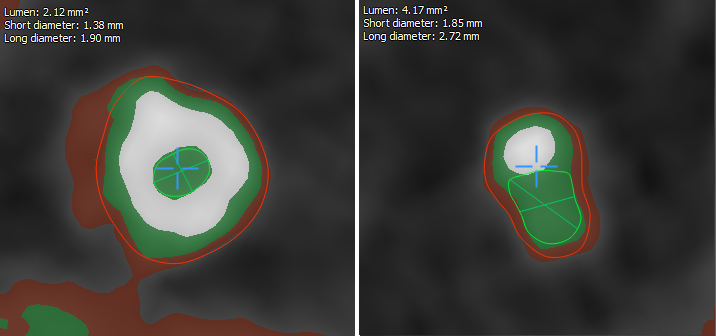

Как мы можем использовать эти знания по отношению к сосудам? Давайте взглянем на структуру одного из них:

На схемах этот момент обычно опускают, но в сосуде могут также присутствовать жир и образования кальция. Таким образом каждый воксель будет принадлежать к одной из тканей. После экспериментов оказалось что достаточно сделать следующие деления:

— жир

— стенка #1

— стенка #2

— контрастное вещество

— кальций

Распределение интенсивностей вокселей в каждом случае является нормальным. Т.е. у нас есть всё необходимое, чтобы, используя EM, найти параметры каждого источника.

Зеленая линия — гистограмма интенсивностей, красная — полученная математическая модель.

Теперь, когда мы знаем параметры каждого источника, мы можем вычислить пороги — значения интенсивностей, при пересечении которых, принадлежность вокселя меняется с одного источника на другой. Нас интересуют:

1. Порог внешней границы сосуда. Если интенсивность вокселя ниже этого значения, то считается, что он вообще не принадлежит сосуду;

2. Порог внутренней границы сосуда. Если интенсивность вокселя больше этого значения, то он

относится к просвету сосуда, т.е. к смеси крови и контрастного вещества;

3. Порог кальция. Если значение интенсивности вокселя больше этого значения, то он относится к кальцию.

Если визуально отобразить данные согласно порогам, полученным на предыдущем этапе, мы получим такую картину:

Красный цвет — стенка сосуда. Зеленый цвет — просвет. Белый цвет — кальций.

Первое, что бросается в глаза — это “висячий” кальций, который не примыкает ни к одной из стенок. Это считается нормальным и возникает вследствии сглаживания, применяемого самим томографом.